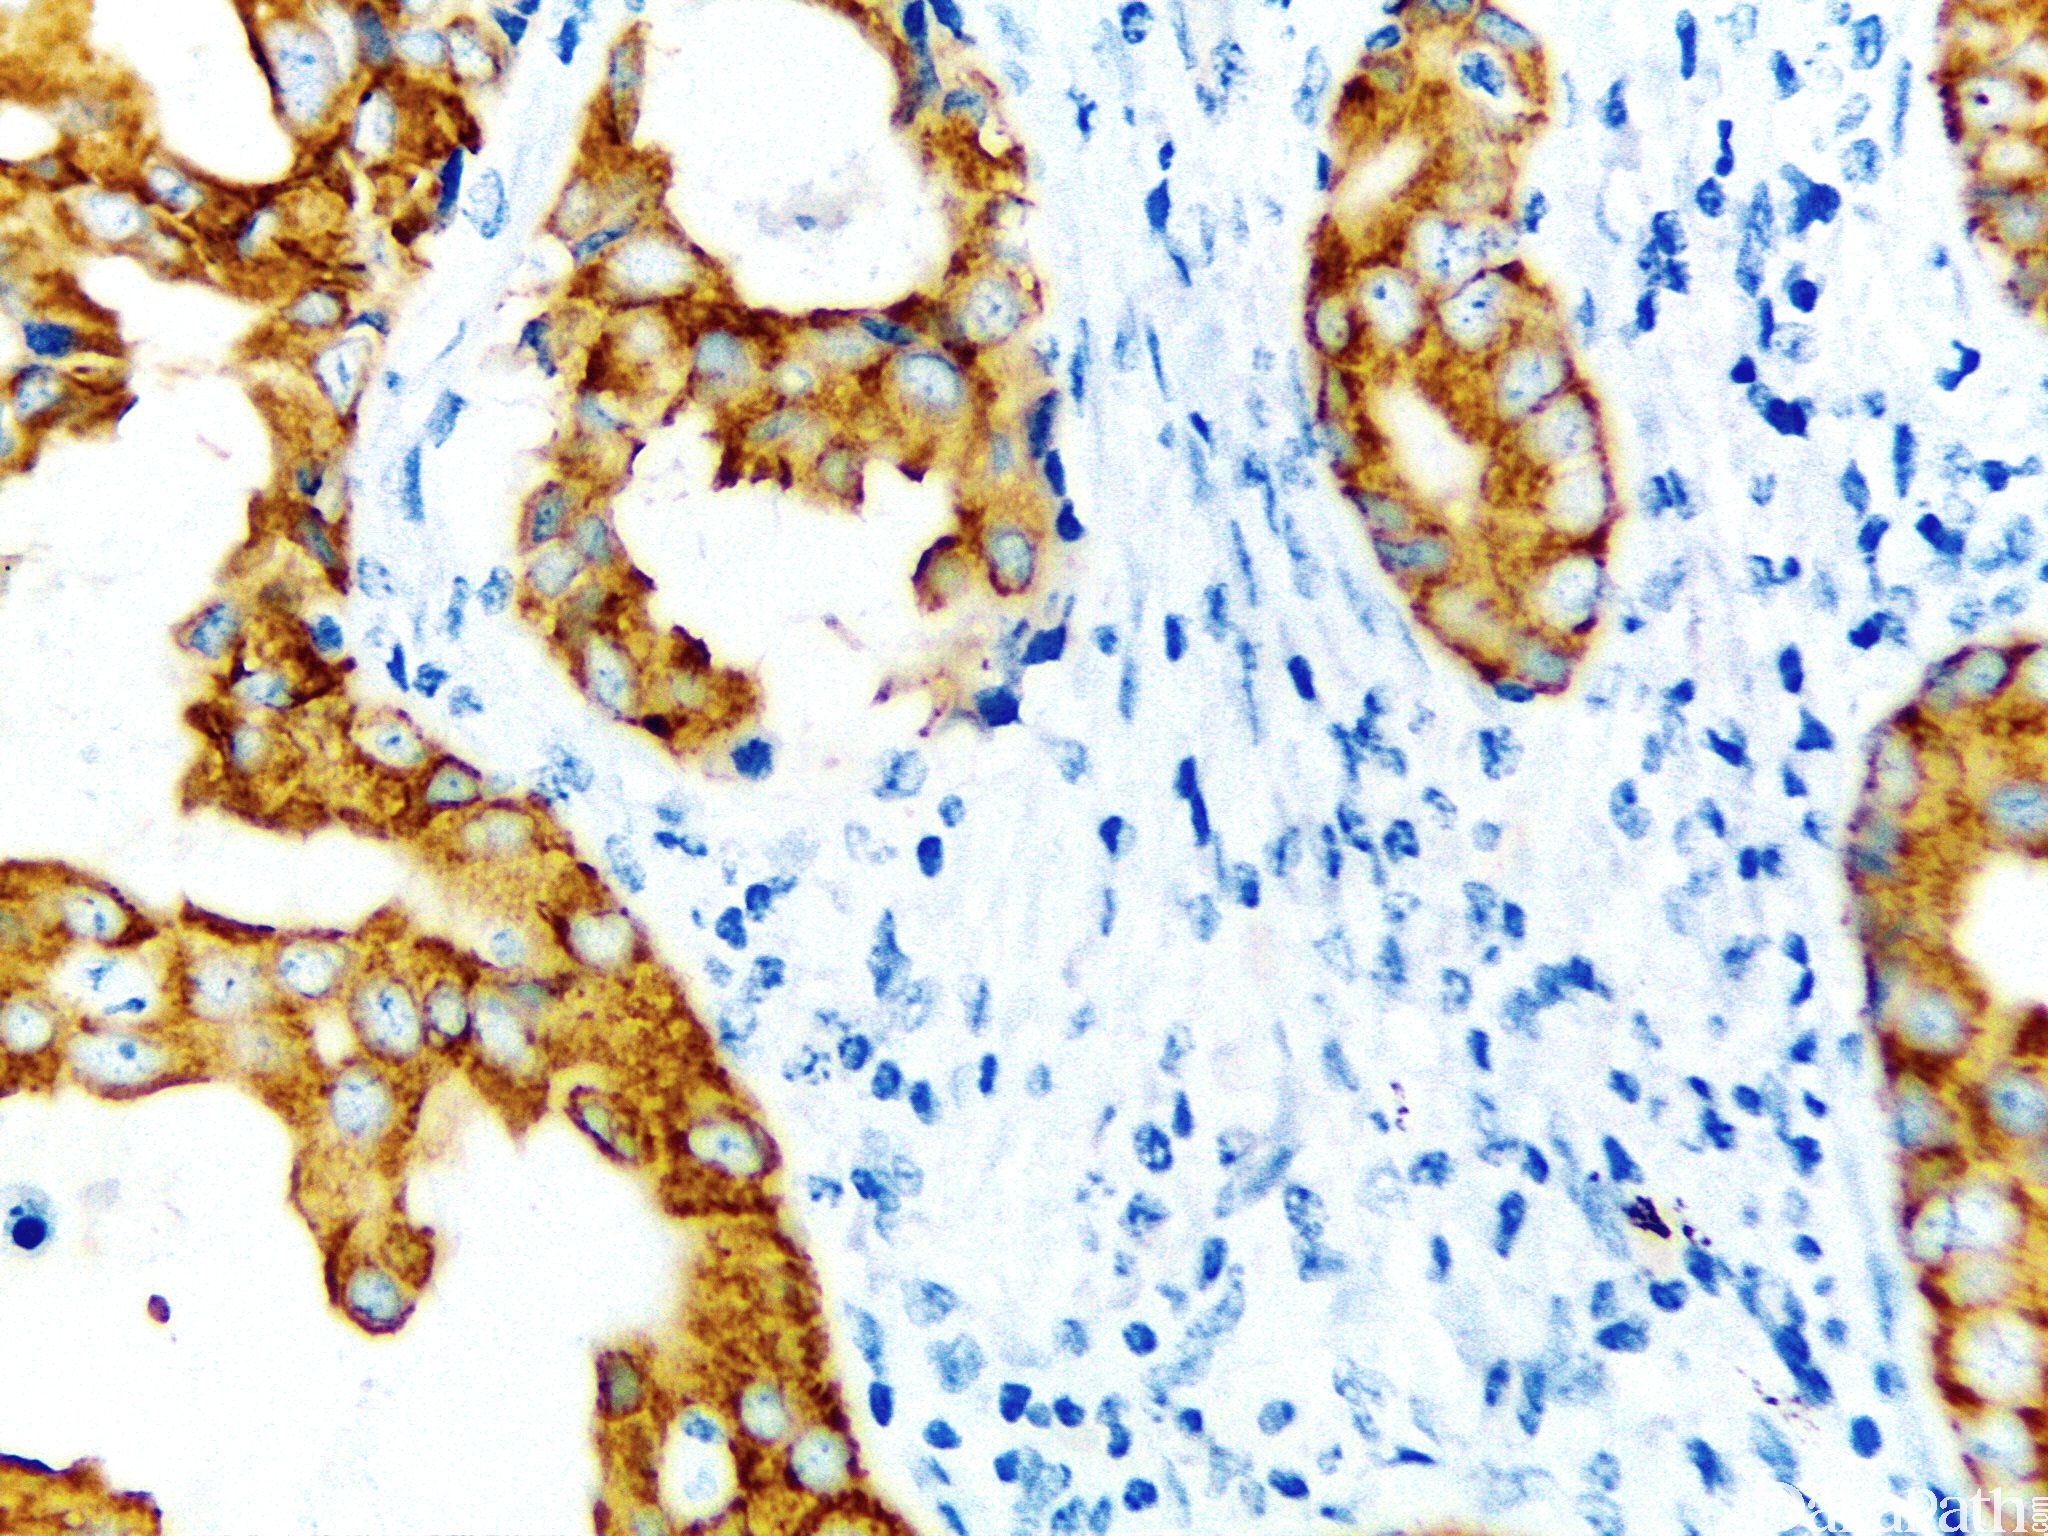

IMP3 是一种致癌胎儿蛋白,属于胰岛素样生长因子 II mRNA 结合蛋白(IMP)。在成人组织中,IMP3 低表达或不表达,但在恶性肿瘤中,如在胃、结肠、胰腺、肺、肾细胞和肝癌中存在过表达。

信号定位: 胞浆